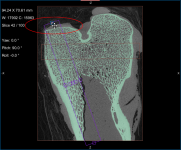

Screen capture of the completed tutorial

In this section, you will learn how to extract the required region of interest from a threshold range. Instructions for refining the initial segmentation are also included here.

- Create a region of interest with data values thresholded for mineralized bone as follows:

- Drag the left or right Range sliders to change the minimum or maximum values of the intensity range or enter the required values in the Min and Max edit boxes.

- Verify the selected range on other images in the image stack and other views of the dataset, recommended.